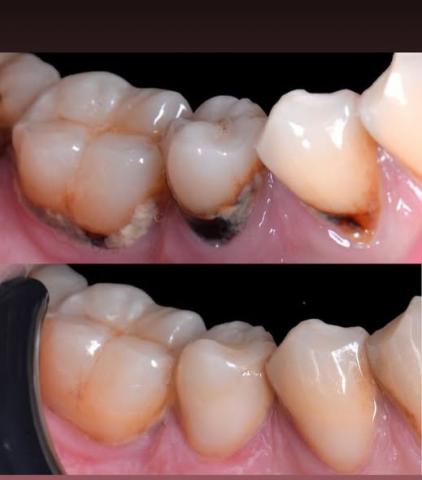

Case Analysis: Cervical Caries (Zoom 100%)

In this dental case, decay is visible near the cervical area — the region where the crown of the tooth meets the gum line — rather than on the chewing surface or fissures. Cervical caries are often overlooked, but they can progress silently and cause significant tooth sensitivity or even nerve damage if untreated.

A clinical and radiographic examination confirms the extent of the lesion. The image shows darkened cervical areas, indicating demineralization and bacterial invasion, which were later restored with composite resin in the lower image.